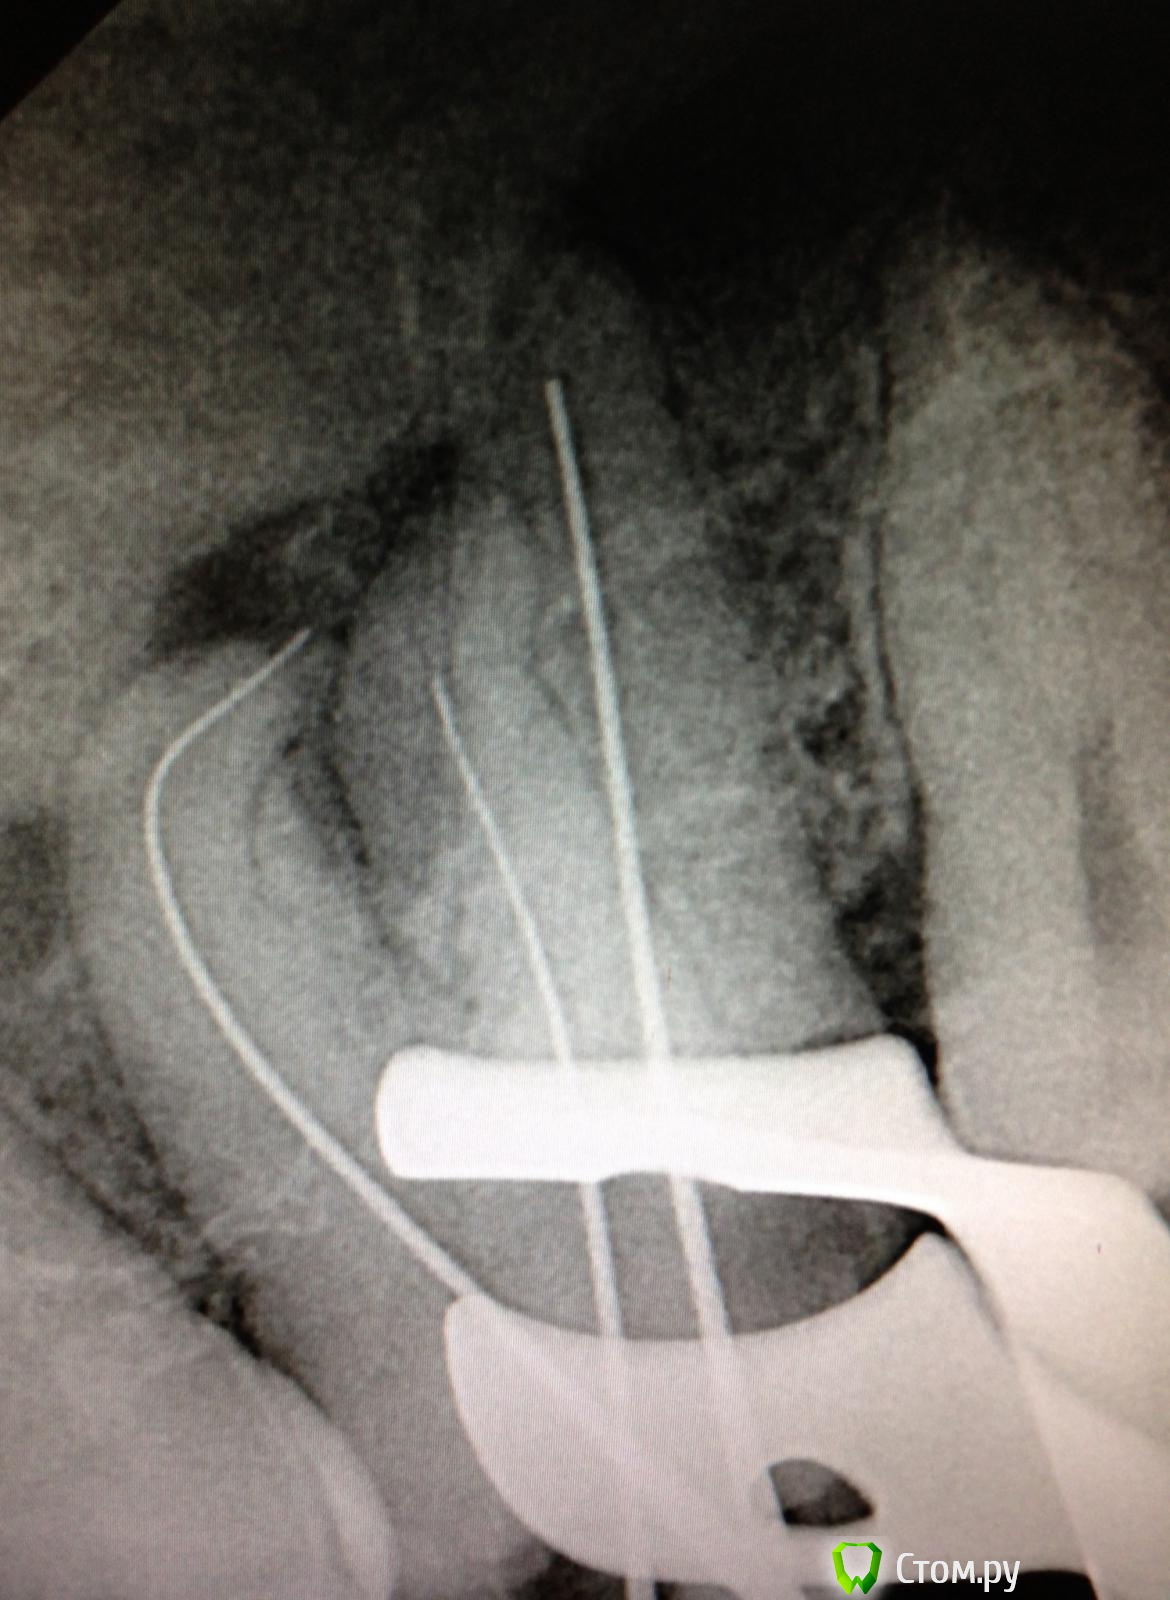

SSTi Опубликовано 19 сентября, 2014 Автор Поделиться Опубликовано 19 сентября, 2014 Новая кривулина. Начало. Попросил доктор знакомый полечить...)Неделю боли на накусывание. Иррадиируют в левый висок. Зуб 27. Внешне все ок. Маааленькая точечка в фиссуре. Шестерки нет. Делаю снимокТааааак. Позвонил доктору, сказал , как я счастлив, и приступил. Преп. Коффер. Дистально на уровне десны. Небный дистальный бугор ушел. В полости небольшой склероз. Мб сразу прошелся. Вообще без проблем. Только при хрусте файлов я чуть вспотел в области крестца))) расширились до 30.04 и дальше ручками 35.02. Мб 2 пока не нашел. Сулькус раскрыл - но там глухо. Поищем в следующий раз. Дистальный сначала только до уровня , как на снимке, потом прошел. Тоже 30.04 и 35.02. Небный- последние 3-4 мм дались с трудом. Но прошли. До 35.04 и 40.02. Мылись, сушились, кальцифицировались. Времянка. Продолжение следует 3 Ссылка на комментарий